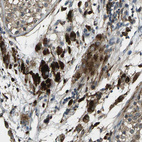

Immunohistochemical staining of human salivary gland shows strong cytoplasmic positivity in glandular cells.